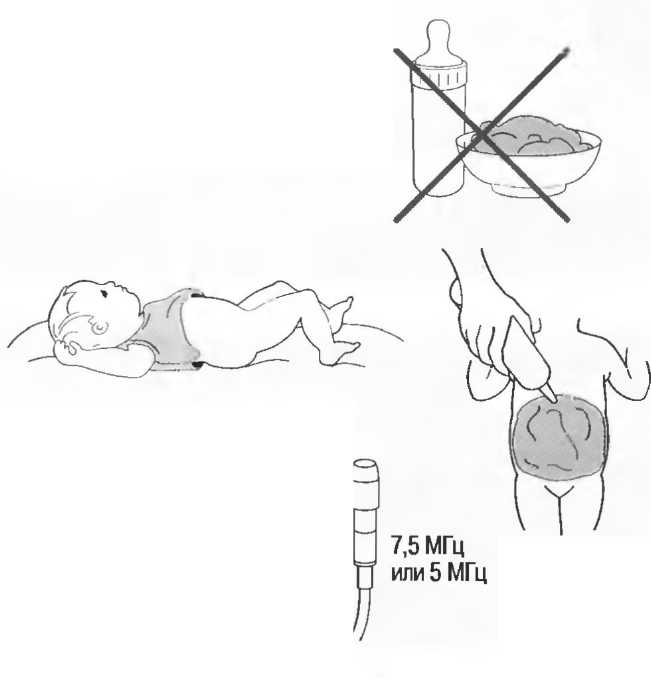

3. Ультразвуковые исследования в педиатрии. Для детей необходим датчик с частотой 5 МГц с глубиной фокусировки на 5-7 см. При исследовании мозга новорожденного используется секторный датчик с частотой 7,5 МГц с глубиной фокусировки на 4-5 см (этот датчик также используется для исследования яичек и структур шеи у взрослых).